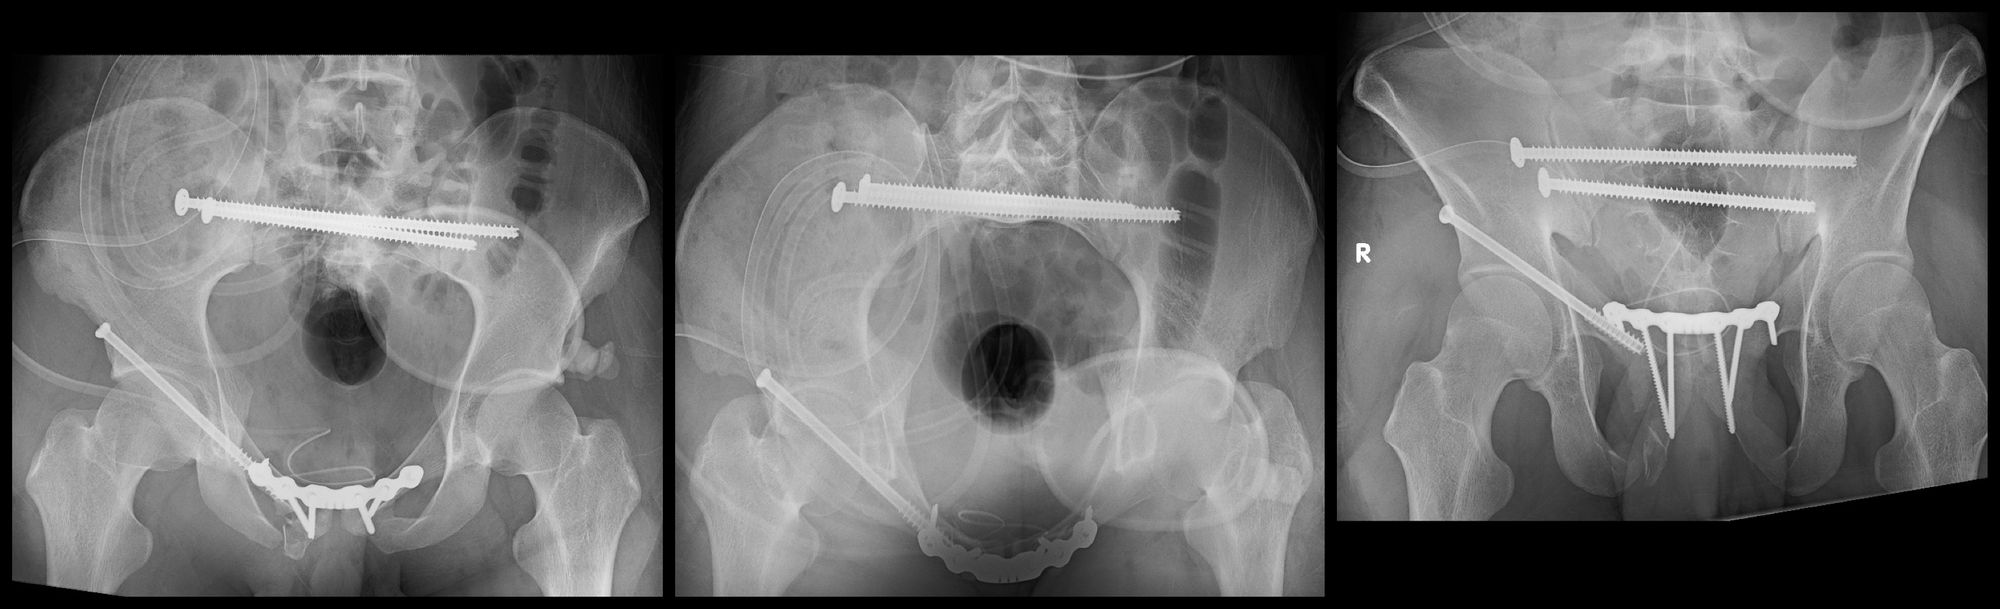

Percutaneous fixation of pelvic fractures—introduction

Percutaneous fixation of pelvic fractures—introduction What Is A Pelvic Fixation Pelvic fixation is a surgical technique used to stabilize spinal fusion constructs at the base, or foundation of the spine anchored in the boney. Pelvic fixation is most frequently indicated in the pediatric population for the treatment of neuromuscular scoliosis with. The goals of this review are to describe the history of and. For initial emergent application, pelvic clamps have.. What Is A Pelvic Fixation.

Percutaneous fixation of pelvic fractures—introduction What Is A Pelvic Fixation The goals of this review are to describe the history of and. Both external (outside the skin) and internal (located in or on the bone). External fixation of the pelvis is indicated for temporary or definitive stabilization of unstable pelvic ring injuries. Pelvic fixation is most frequently indicated in the pediatric population for the treatment of neuromuscular scoliosis with. External. What Is A Pelvic Fixation.